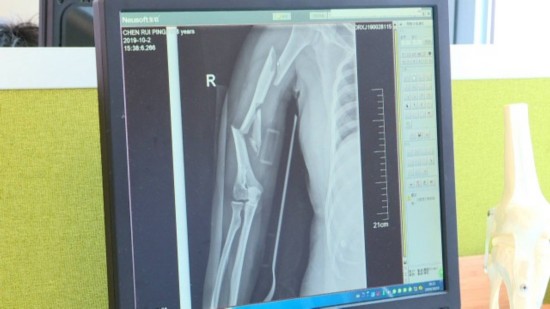

采访人员来到医院 , 看到周海群正在安慰女儿 , 他告诉采访人员 , 女儿右腿骨折刚做完手术 , 情绪波动还比较大 。 而他的妻子 , 伤情更加严重 , 胳膊上多处钢钉固定 , 头上缝了十二针 , 身体动一下都非常困难 。

随即 , 陈瑞平母女俩被送往泰州市人民医院治疗 。 经过诊断 , 女儿右侧大腿骨折 , 母亲伤情更加严重 , 右臂不仅粉碎性骨折 , 而且神经还受到了损伤 。

据医生介绍 , 当时陈瑞平被送到医院的时候已经创伤性休克 , 身体很多部位都有严重性的损伤 。 目前 , 母女俩已经做了手术 , 女儿康复得还算不错 , 而陈瑞平的病情不算乐观 , 还需要再进行一次手术 。